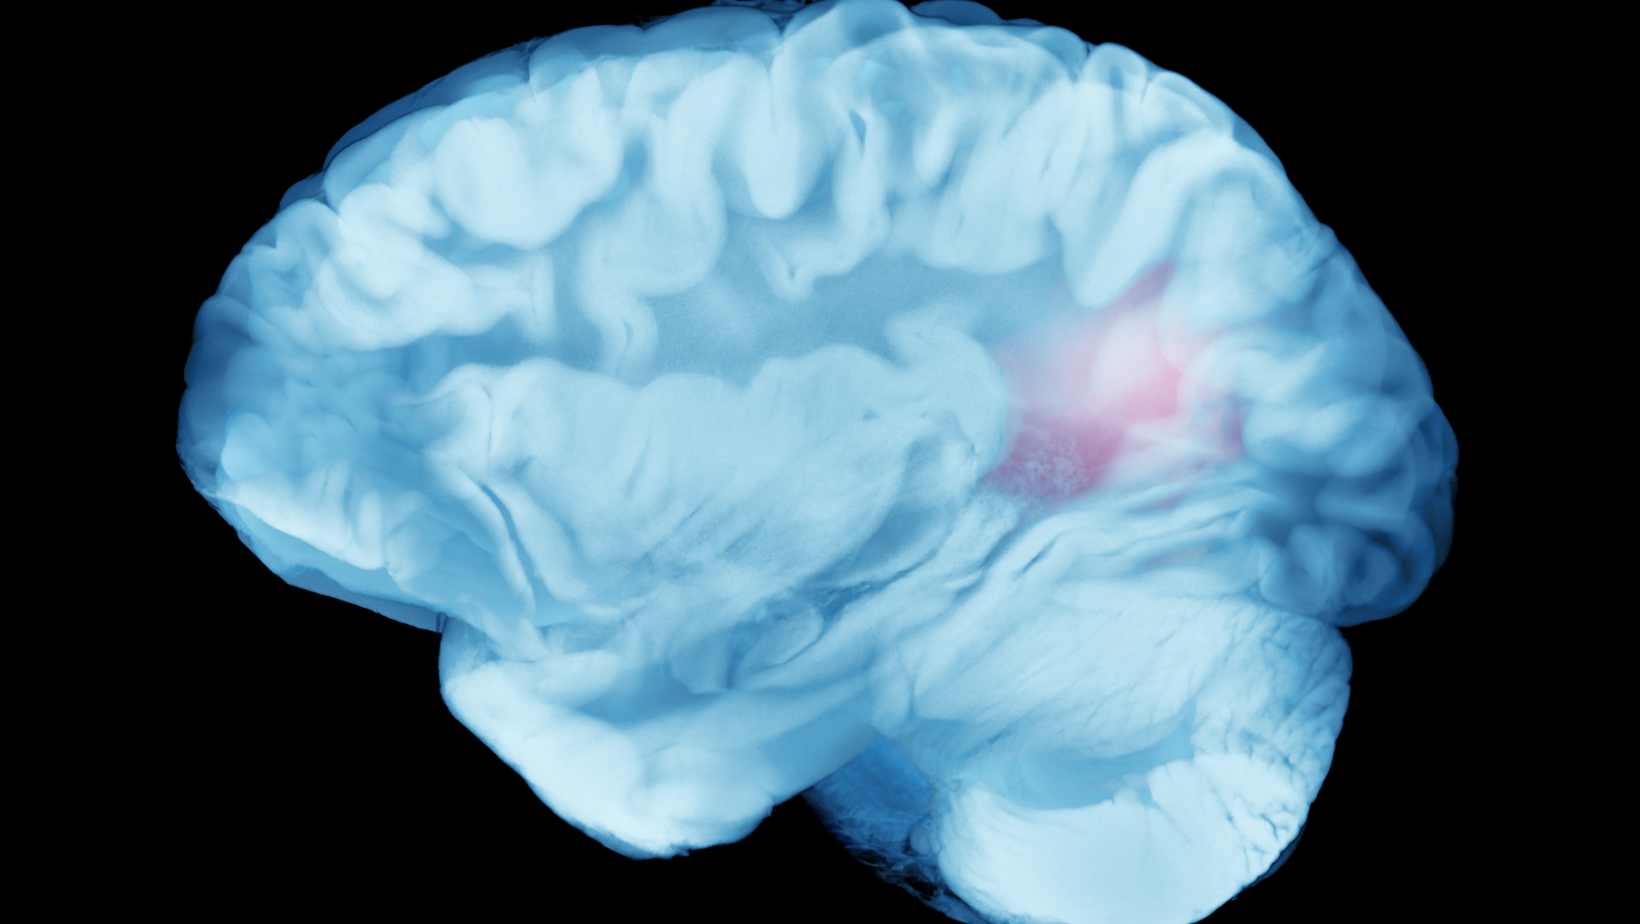

Is There Such a Thing as a ‘Migraine Brain’?

Migraine brain is a term doctors and researchers use to describe the brain of…

Brain Lesions: Causes, Symptoms, Treatments

Brain lesions are areas of damage in the brain tissue, and understanding them…